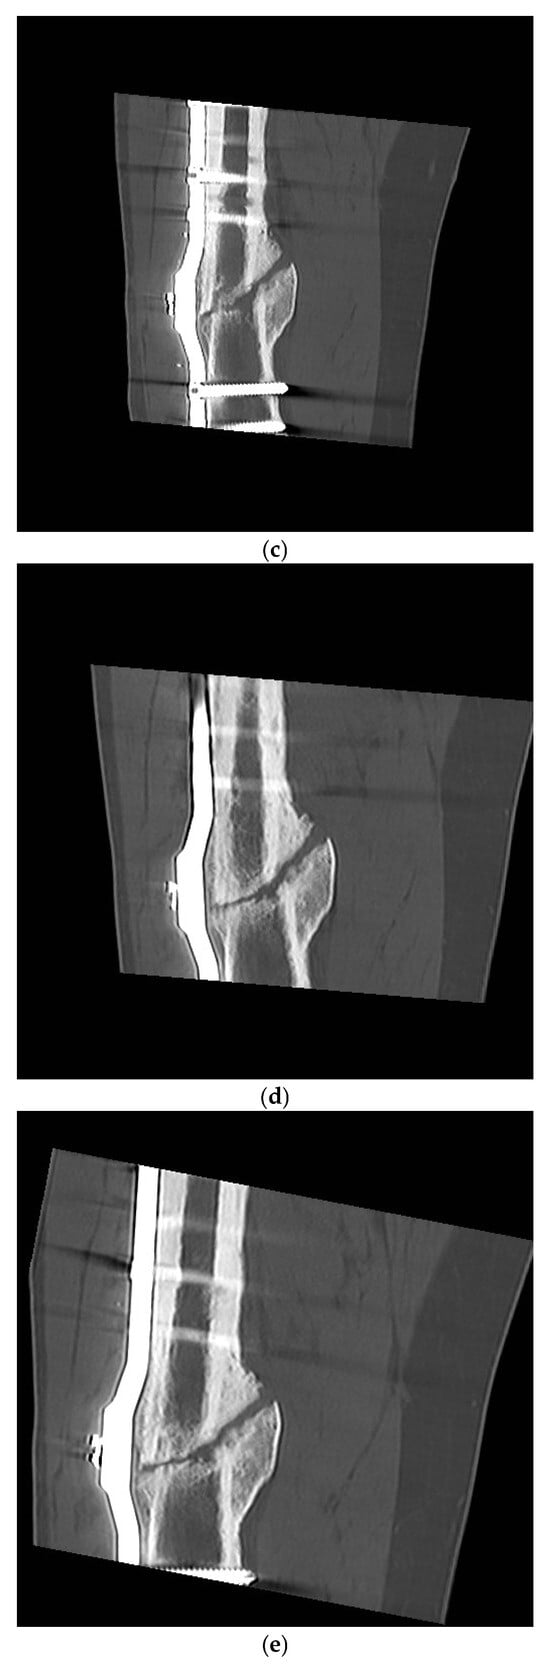

Long-Term Evaluation of Bone Healing Monitoring Using an Instrumented Plate with Measurement Sensors (Smart Implant) over 10 Years

by Arndt P. Schulz, Birgitt Kowald, Matthias Münch, Klaus Seide, Nils Weinrich, Tobias Barth and Benjamin Kienast

Sensors 2025, 25(18), 5779; https://doi.org/10.3390/s25185779 - 16 Sep 2025

A total of 66 smart implants were included. As a measure of bony stability, the relative elastic compliance of the osteosynthesis was determined from the gradient between the applied external load and the measured implant load over the entire healing process. The healing [...] Read more.

A total of 66 smart implants were included. As a measure of bony stability, the relative elastic compliance of the osteosynthesis was determined from the gradient between the applied external load and the measured implant load over the entire healing process. The healing process of non-unions of the femur with a smart implant was tracked by telemetric measurements over a timespan of up to 10 years. The measurements of the longest healing process show a very slow but constant decrease in force transmission over the implant, radiological findings over 10 years show corresponding consolidation until bony healing. The use of a telemetrically instrumented bone plate, a so-called smart implant, to monitor the healing process is a successful procedure to support the clinician in his decision to take further surgical measures or to wait until healing occurs. Full article